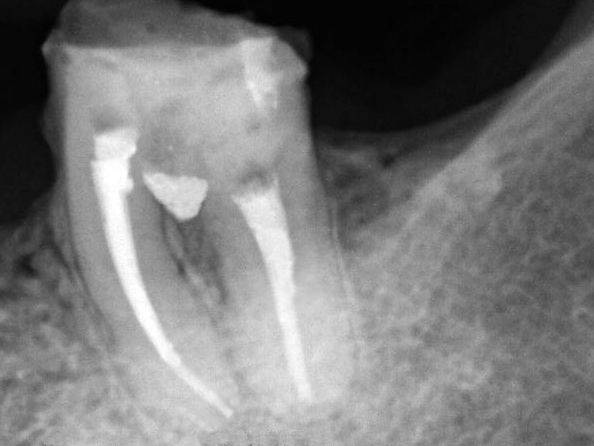

Após 15 dias, procedeu-se o selamento da região da perfuração, sendo inicialmente constatada a possibilidade adequada de secagem da região. O preenchimento da perfuração foi realizado com o emprego do MTA Repair HP (Angelus/Brasil), previamente preparado, conforme recomendação do fabricante, sendo o mesmo inserido com uso de aplicador de MTA (Angelus/Brasil).

Os critérios clínicos e radiográficos foram utilizados para determinar o correto preenchimento pelo material (figuras 4 e 5), sendo o cimento de ionômero de vidro (Vitremer/3M/EUA) empregado para a proteção da região selada (figura 6).

Após a restauração provisória, observou-se radiograficamente um adequado selamento da região de furca pelo MTA Reapair HP, bem como a presença de pós-operatório silencioso.